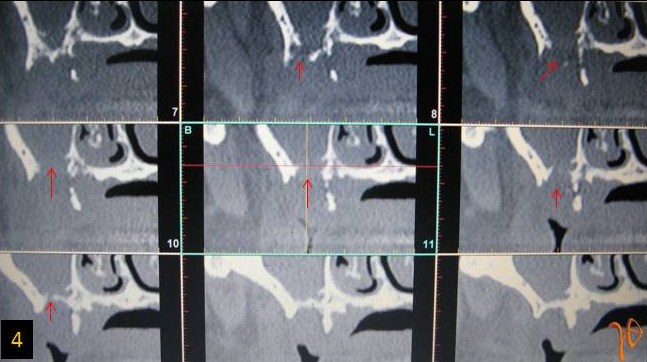

Οι πιο συχνές βλάβες από ερεθισμό στο στόμα είναι τα αντιδραστικά ινώματα (Εικόνες 4 και 5).

Εικόνα 4. α. Ίνωμα της υπερώας από χρόνιο ερεθισμό ολικής οδοντοστοιχίας (βέλος), β. Μετά την χειρουργική του αφαίρεση.